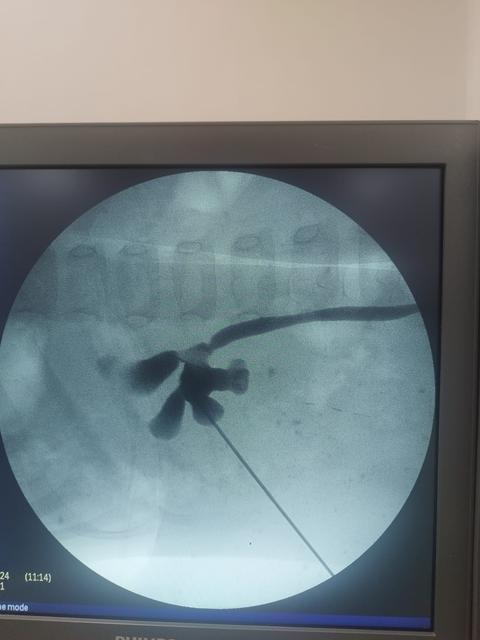

Elazığ Fethi Sekin Şehir Hastanesi'nde, Bingöl'den gelen 2 yaşındaki hasta, kapalı yöntemle gerçekleştirilen başarılı bir böbrek taşı ameliyatıyla sağlığına kavuştu. Üroloji Kliniği eğitim sorumlusu Doç. Dr. Kadir Yıldırım, özel teknik ve cihazlarla gerçekleştirilen ... haberin devamı için tıklayın

24 AYLIK BEBEKTEN 1.5 SANTİMLİK TAŞ ALINDI: SÜPER MİNİ PNL İLE BÜYÜK BAŞARI